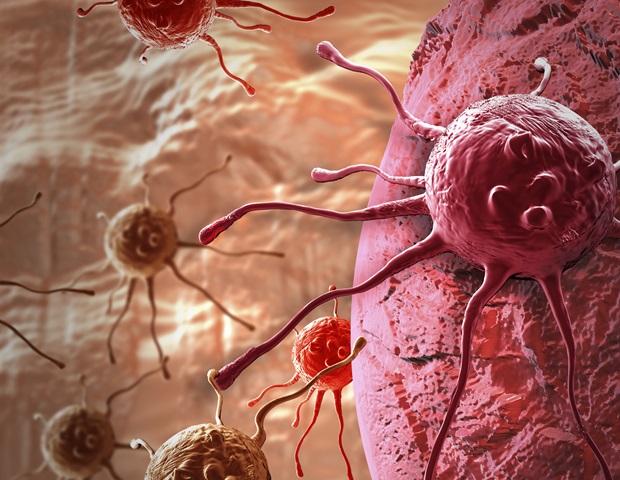

צמד תרופות שגורמות לתאים ממאירים לפעול כאילו יש להם וירוס עשויות להוות הבטחה חדשה לטיפול בסרטן המעי הגס וגידולים מוצקים